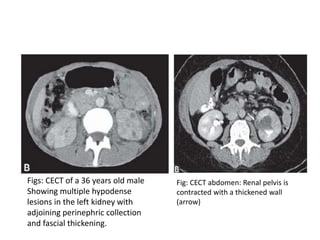

Figs: CECT of a 36 years old male

Showing multiple hypodense

lesions in the left kidney with

adjoining perinephric collection

and fascial thickening.

Fig: CECT abdomen: Renal pelvis is

contracted with a thickened wall

(arrow)